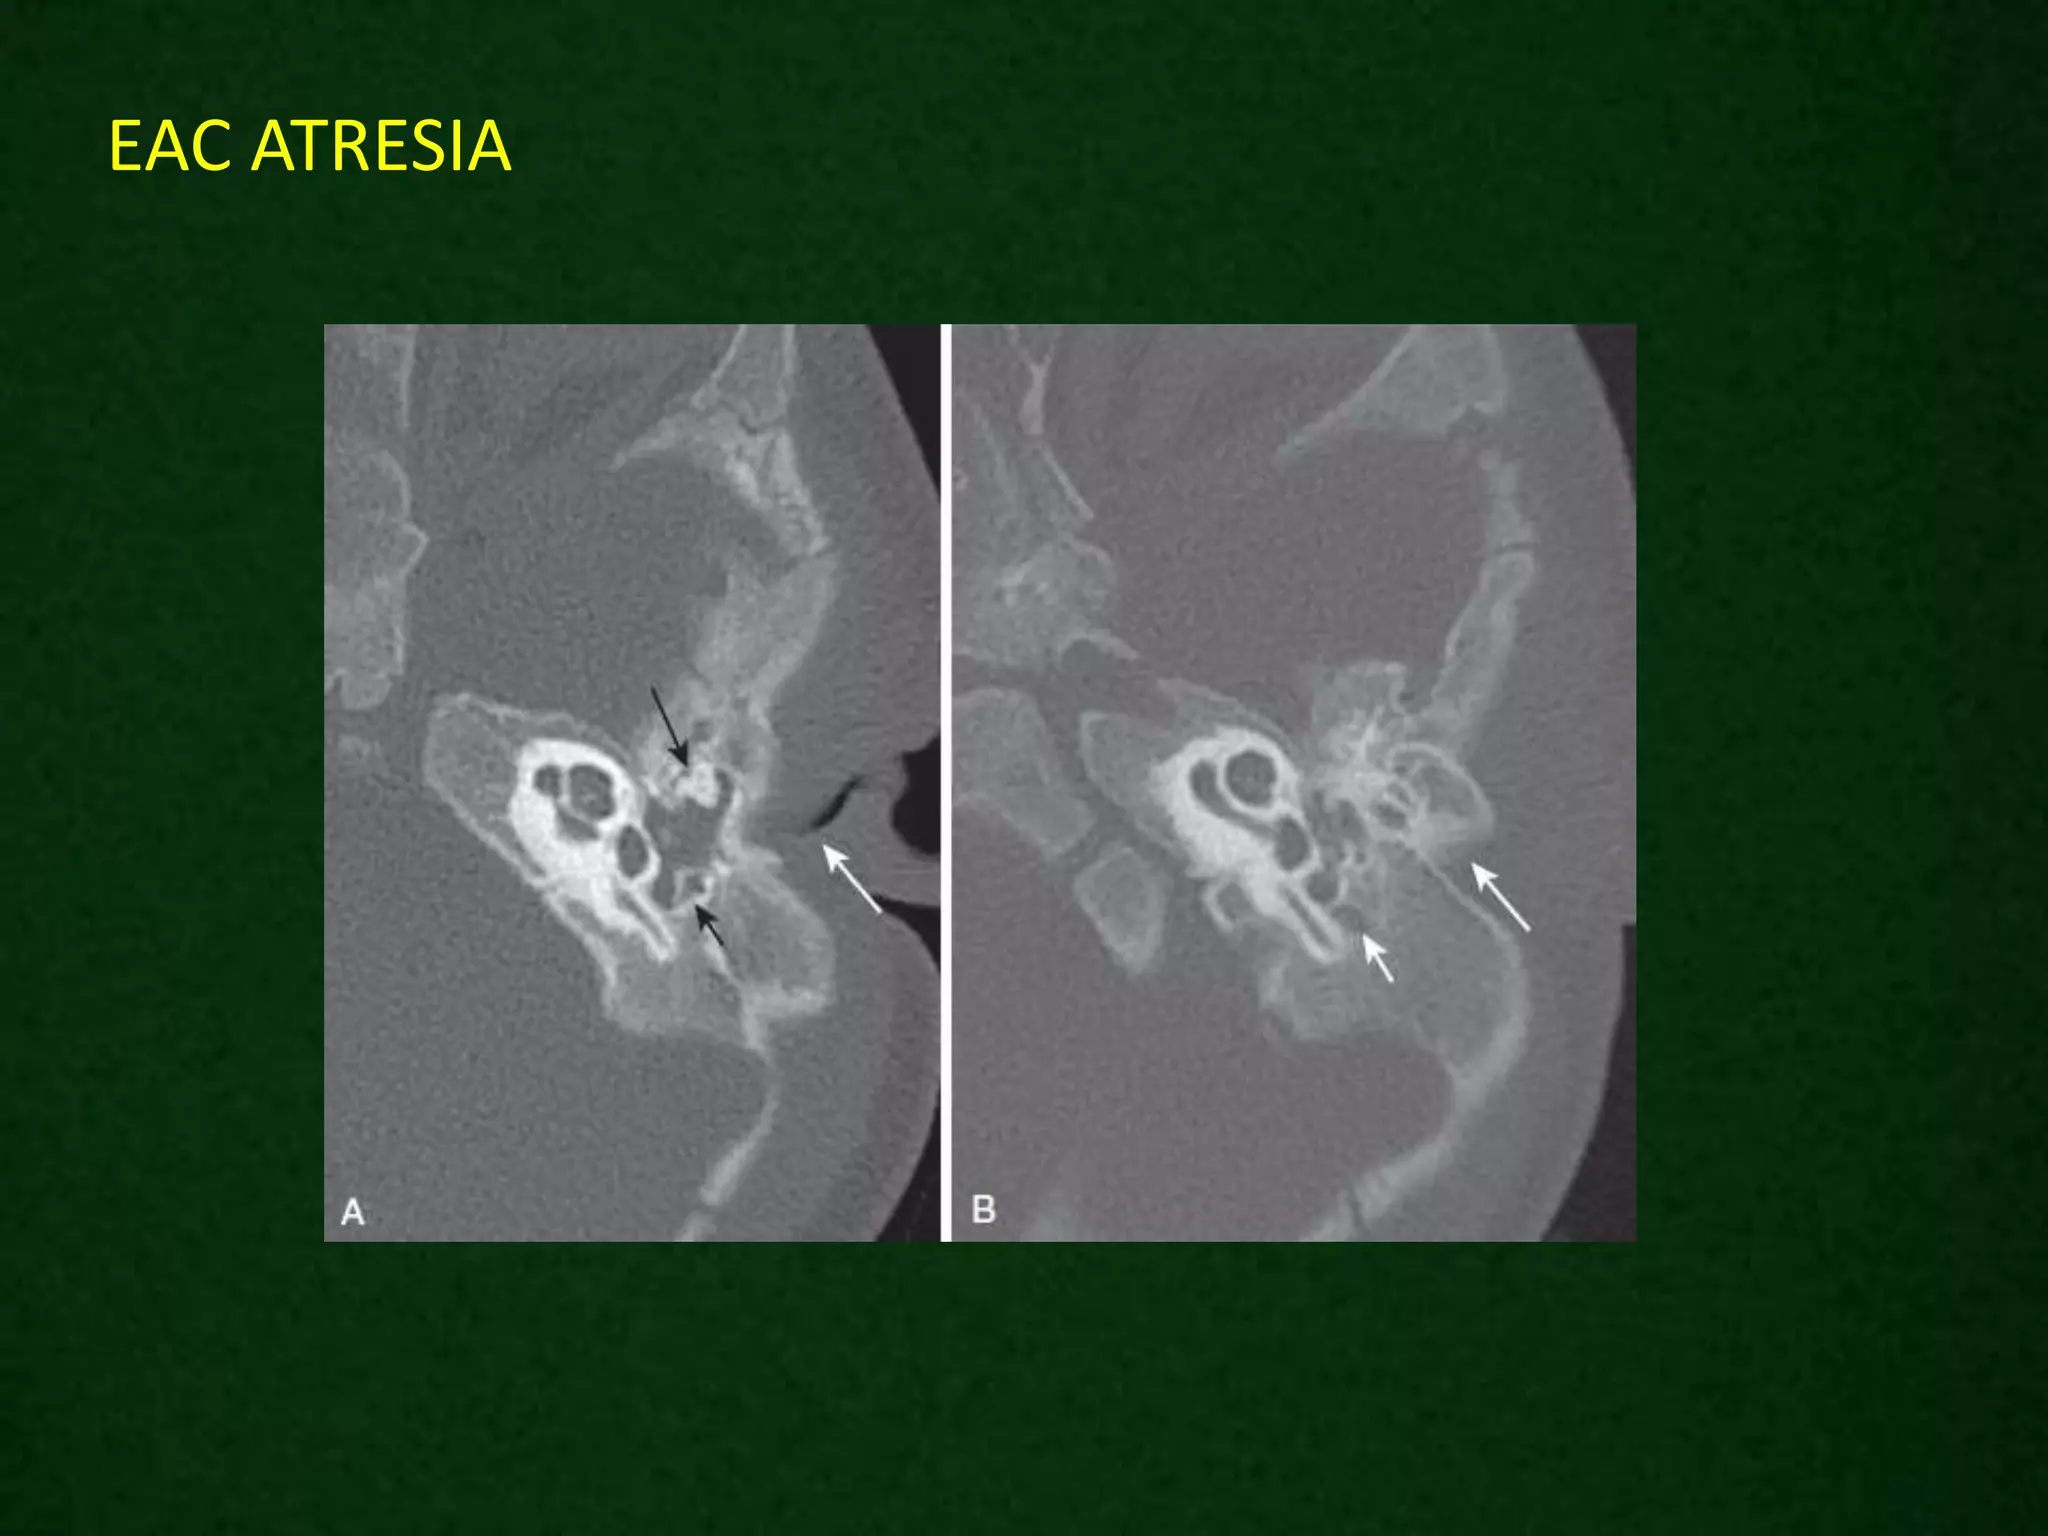

EAC ATRESIA